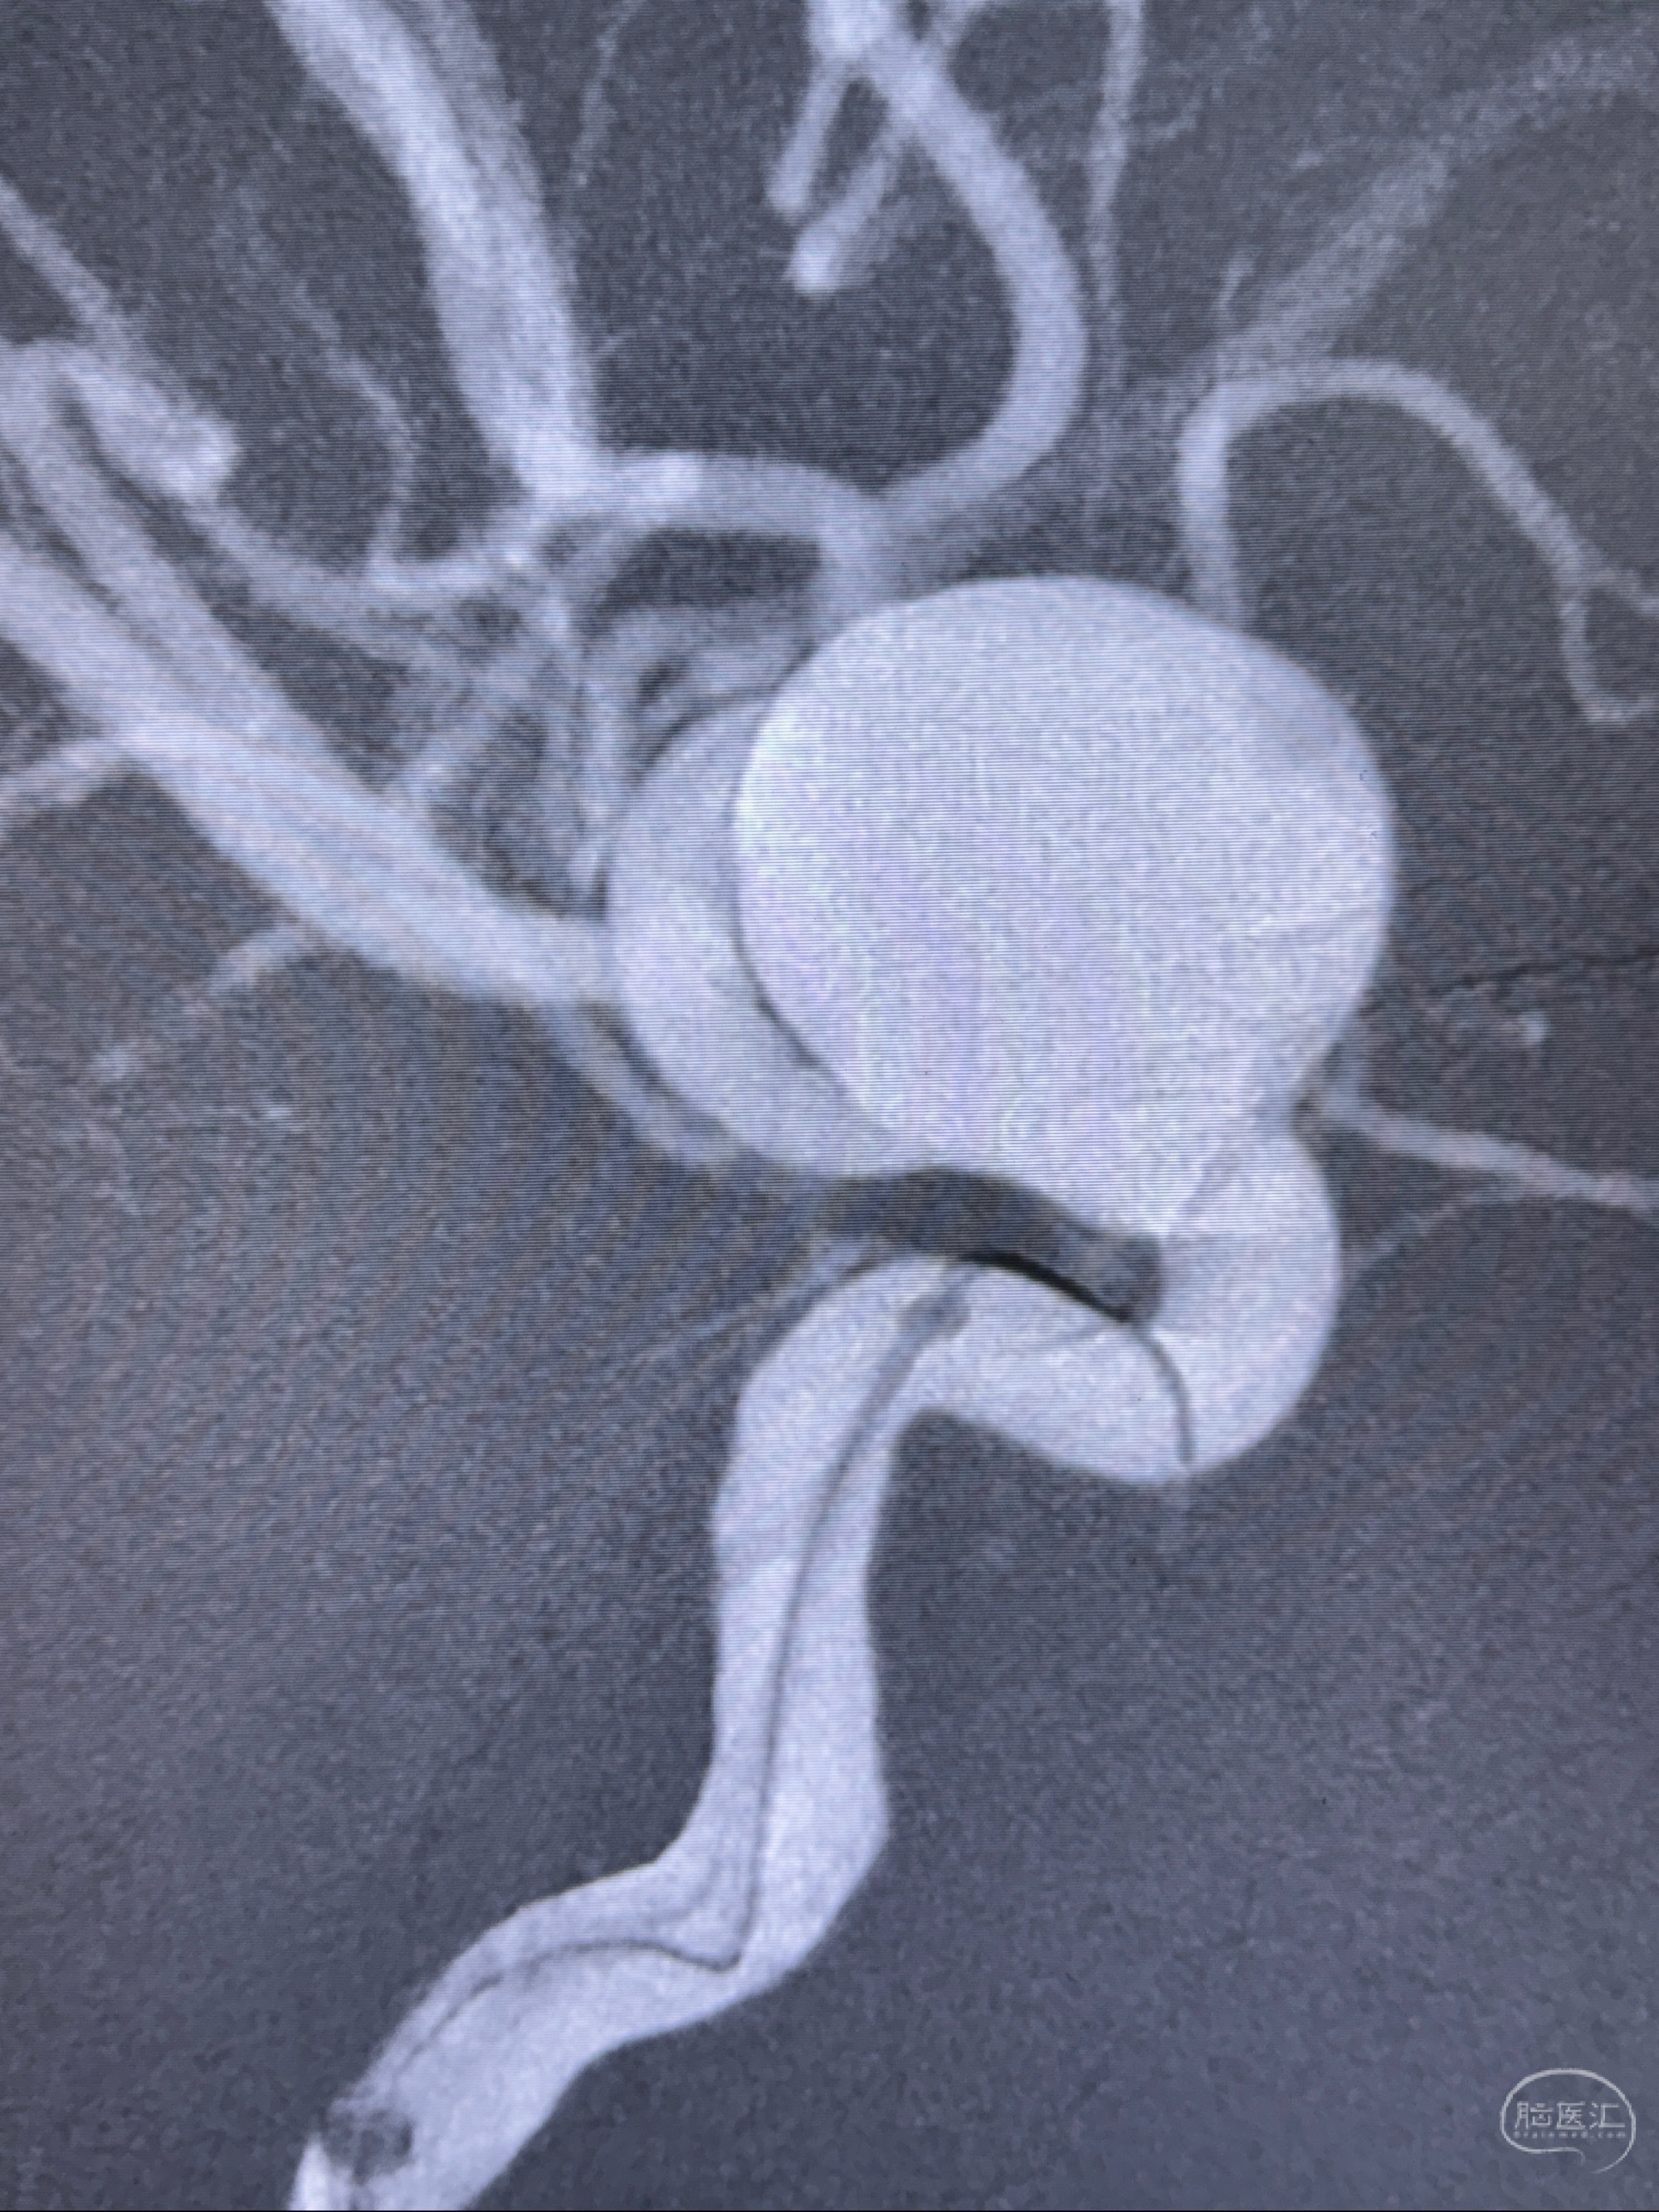

2023-12-27术后第十天复查DSA

支架贴壁佳,但可见射流,咋办?

2024-01-08全麻下再行植入密网支架一枚

Tubridge 4.5-35mm

支架植入顺利,贴壁佳,支架内血流通畅,动脉瘤内血液滞留明显